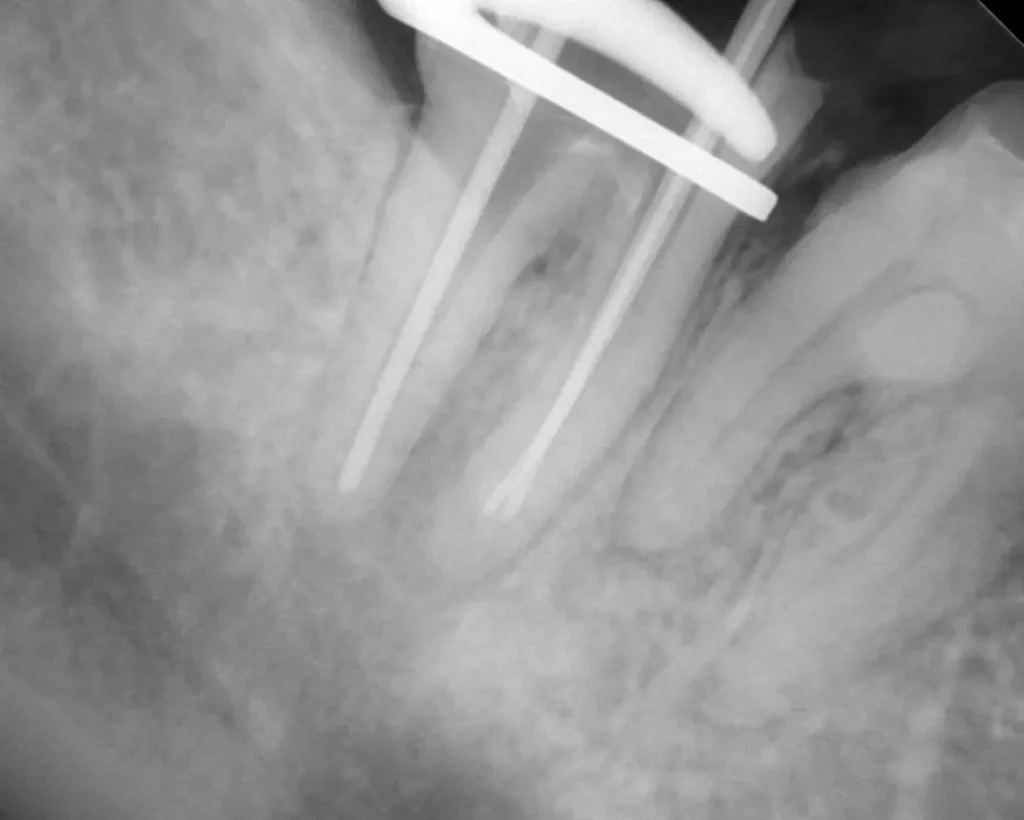

術中(ファイル試適)

レントゲン写真

ラバーダムシートを固定する金具が写っています、シートはバイ菌が

入らないように撮影時にも外しません